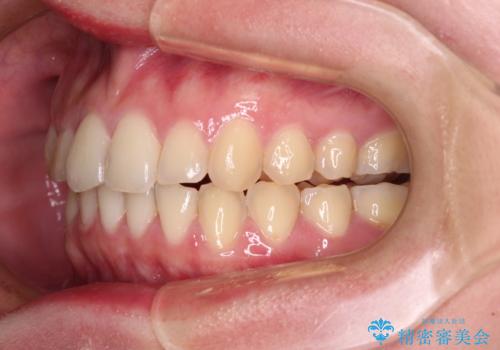

- 食いしばりが気になっていたとのことで来院された患者様です。

当初は睡眠時のマウスピースのみの製作をご希望でしたが、矯正治療の提案をしたところ、インビザラインにて矯正治療を行うこととなりました。

矯正治療中に食いしばりがより強くなることがあるため、半年に1回のペースでボツリヌストキシンによる咬合力緩和を並行して行うこととしました。

咬合力の緩和と食いしばりがちな咬み合わせが改善され、顎の負担が大幅に軽減されました。